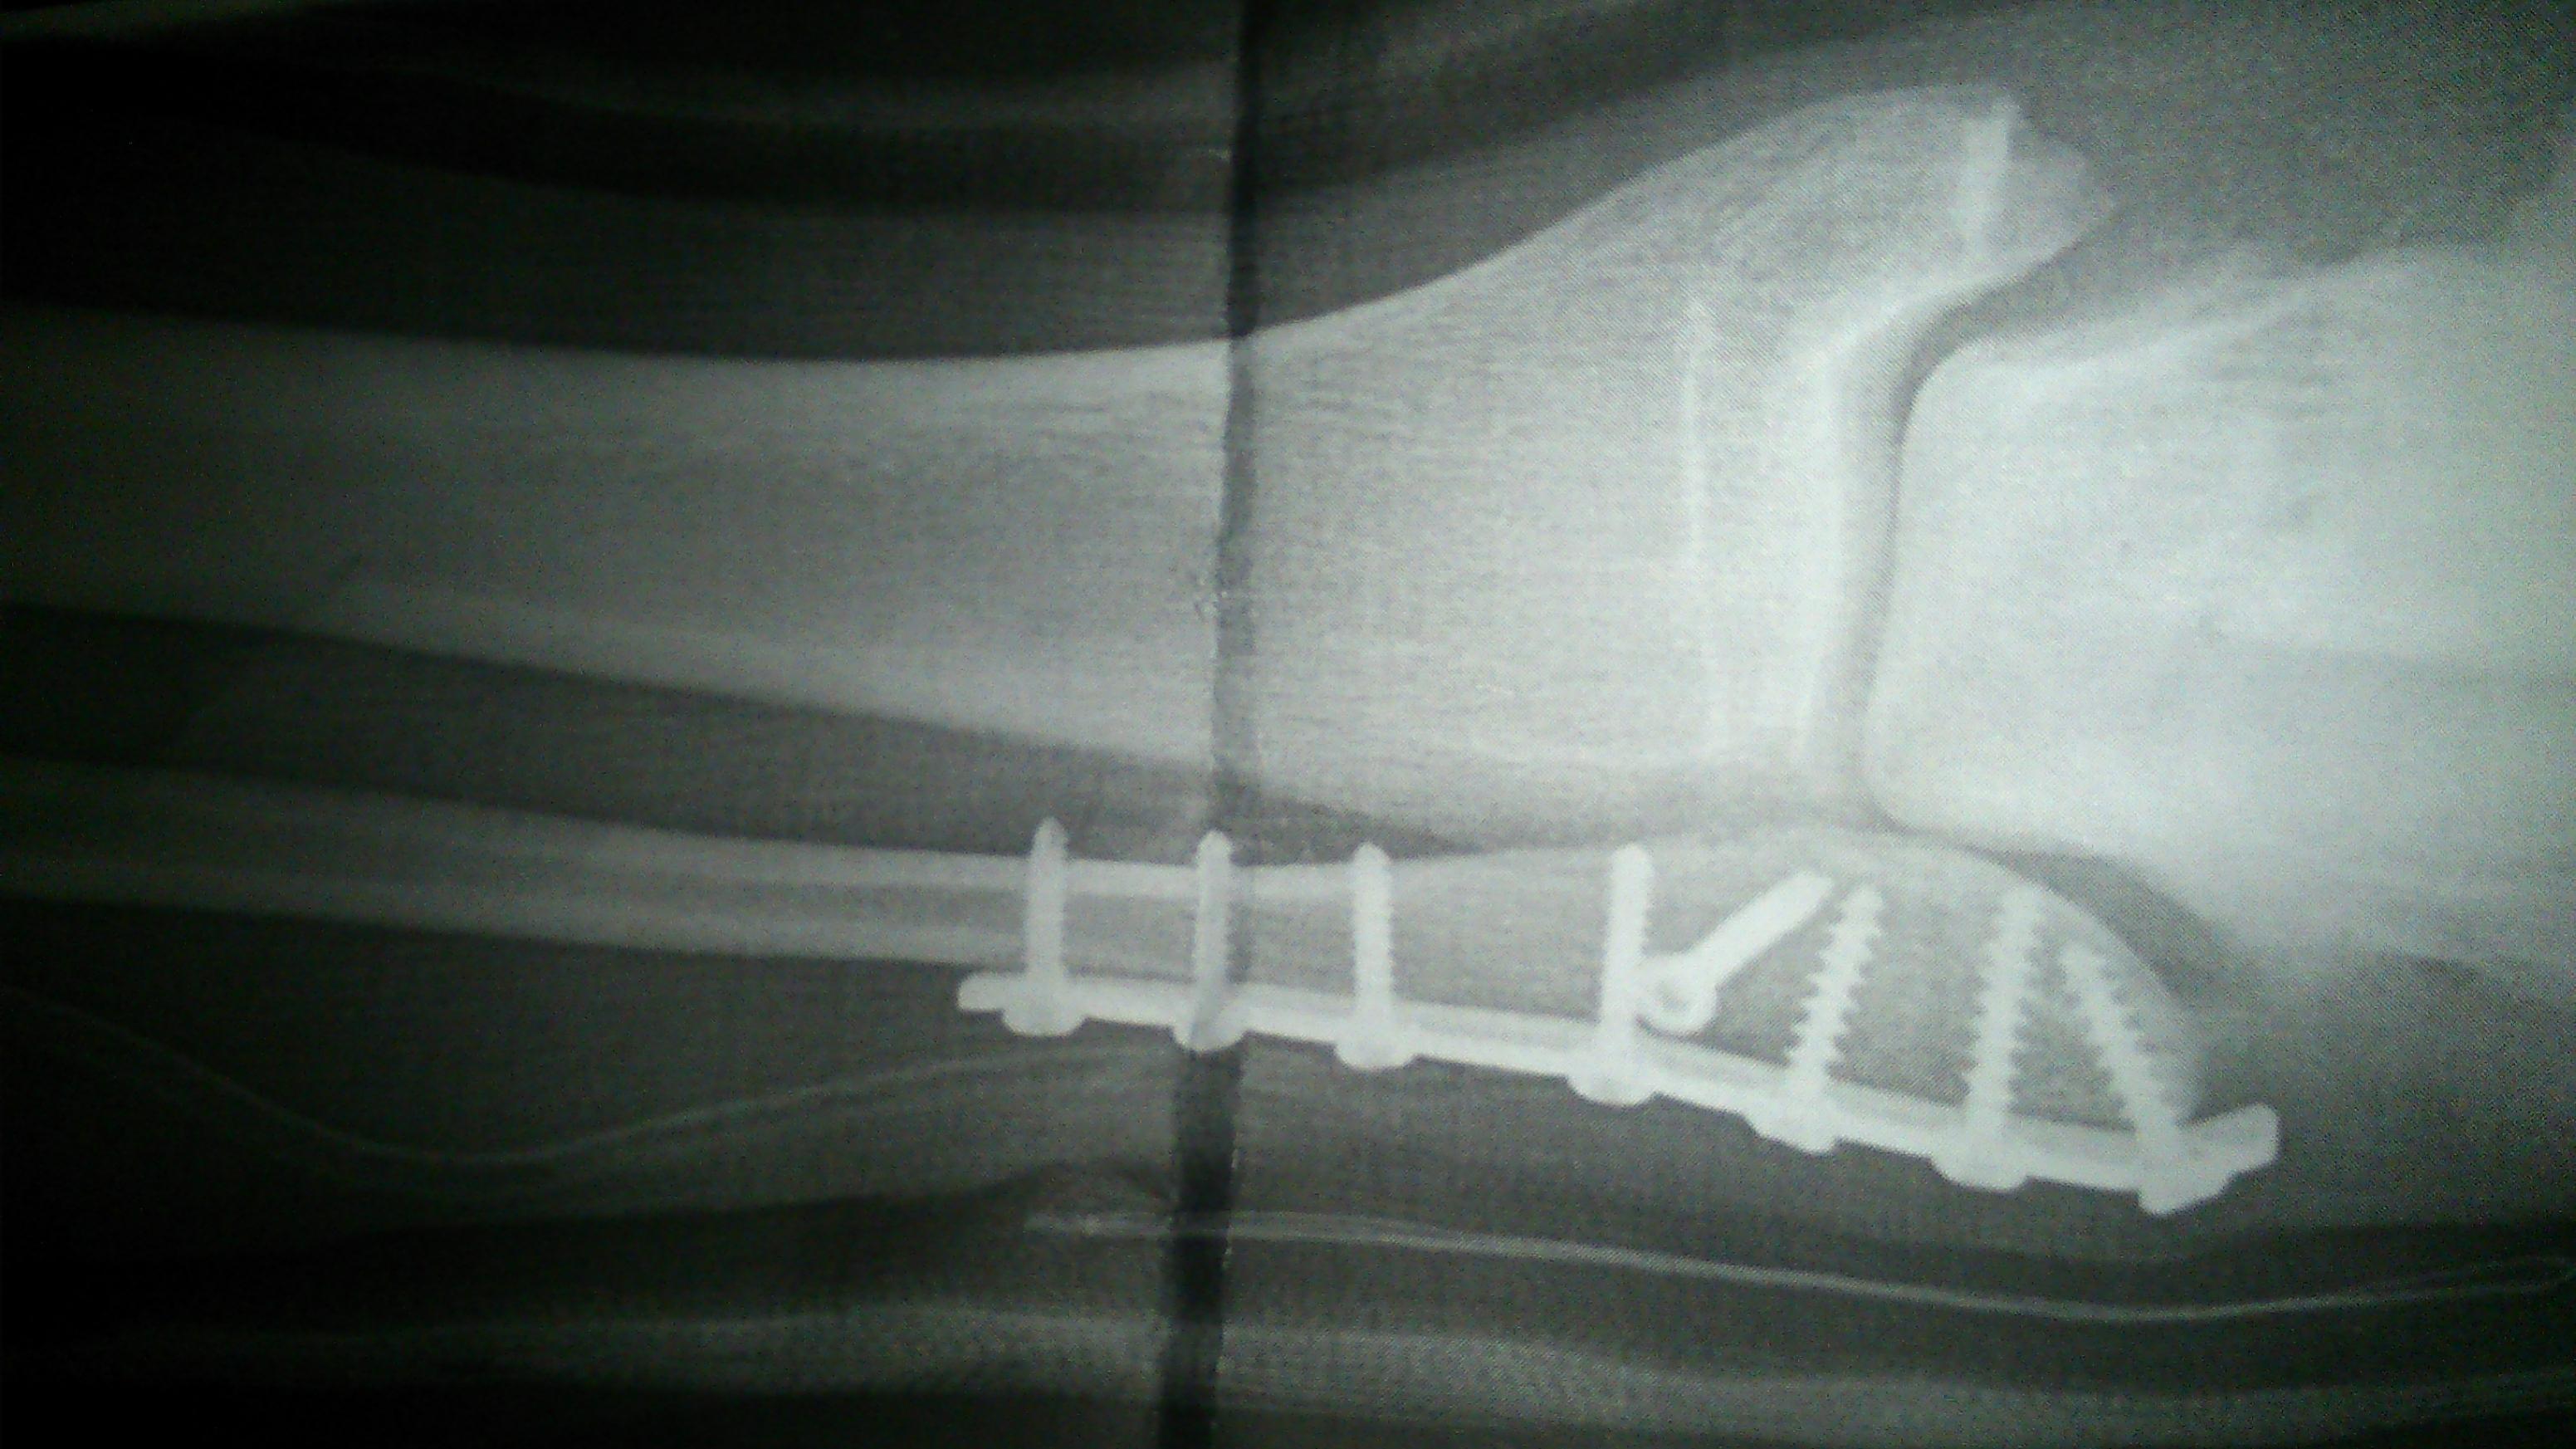

vor 8 Tagen habe ich mir leider eine sogenannte "Weber B Fraktur des Außenknöchels mit geringer Dislokation. Keine Luxation im Sprunggelenk" zugezogen. Vor 5 Tagen wurde ich operiert ( nach 3 Tagen Abschwellzeit) und bekam eine Platte mit insgesamt glaub 7 Schrauben. Diese sollen erst nach einem Jahr wieder entfernt werden.

Gestern wurde ich auf Krücken entlassen (ohne Gips, Schiene oder ähnliches). Nun darf/ soll ich den Fuß ab sofort für die nächsten 6 Wochen mit 20 Kilo beim Gehen bereits belasten und darauf achten, dass ich "abrolle", was aufgrund der Schwellung und Schmerzen bisher aber noch fast unmöglich ist. Bisher lege ich den Fuß fast nur hoch und kühle.

Nach den 6 Wochen sollte ich den Fuß wieder voll belasten.